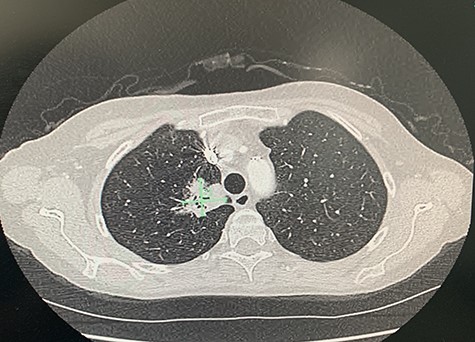

She presented to the operating theatre for excision with incidental dyspnoea and coryzal symptoms, and a pre-operative chest X-ray was arranged before any anaesthetic was administered, revealing a right upper lobe pulmonary mass partly obscured by the clavicle. She underwent excision of the cutaneous lesions, and respiratory physicians were consulted (Fig. 2). Urgent computed tomography (CT) chest was arranged, which revealed the diagnosis of lung malignancy, with a spiculating right apical mass measuring 48 × 30 × 29 mm, extending to the mediastinal pleura and in proximity to the oesophagus and posterolateral trachea with obliteration of the fat planes. There was also local hilar and paratracheal lymphadenopathy, measuring 30 × 29 × 20 mm in the right superior hilar region, 21 × 24 × 13 mm in the right inferolateral hilar region and a 36 × 14 mm pretracheal node (Figs 3 and 4). There were also background mild centrilobular emphysematous changes. There was no metastatic abdominal or pelvic disease.